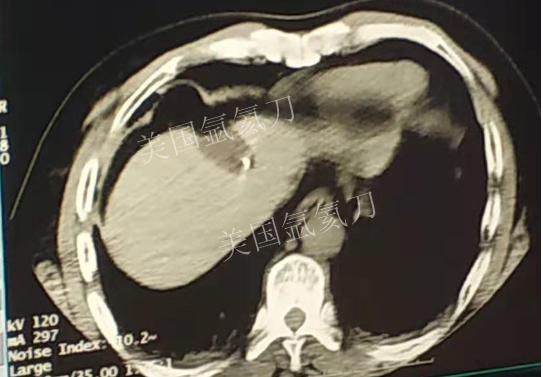

59岁男性肝部氩氦刀手术治疗

发布人:美国氩氦刀技术官方网站    发布时间:2019/3/13 15:42:57